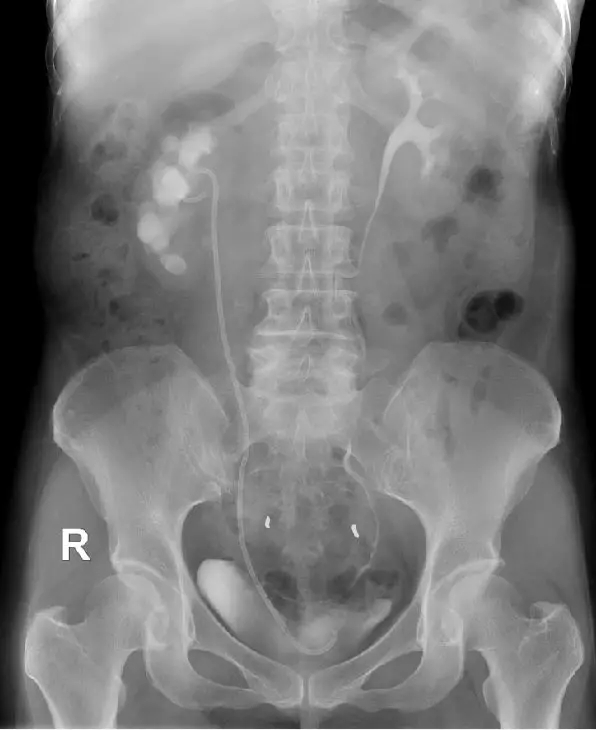

术后1月复查静脉泌尿系造影提示右肾功能良好。为彻底解决输尿管狭窄,避免狭窄复发,经科室讨论,认为输尿管狭窄与开放手术疤痕、反复输尿管结石梗阻、输尿管慢性炎症有关,留置常规输尿管内支架管治疗无效。决定Ⅱ期植入治疗输尿管狭窄的“黑科技”——ALLIUM输尿管支架。手术过程顺利,术后患者康复良好,术后3天顺利出院。

术后复查静脉泌尿系造影提示右肾恢复分泌功能术后提示成功植入Allium支架